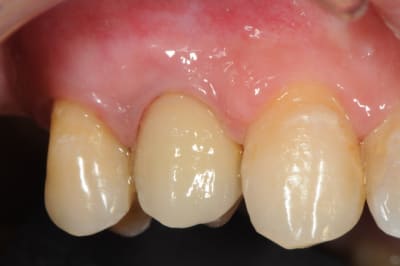

pluton

çà manque un peu de cas en ce moment...alors en voilà un ptit au passage...

11 avec résorption interne

EII avec MCI sur du dentium (4.5/14) comblement du gap vestibulaire avec du kasios tcp (très constant dans les résultats...et très économique)

pas de photos de chir par contre...j'ai du les effacer par erreur...grrrr...

la prothèse d'usage a été réalisée par ma petite associée...mais j'étais là pour superviser et faire quelques photos...;-)